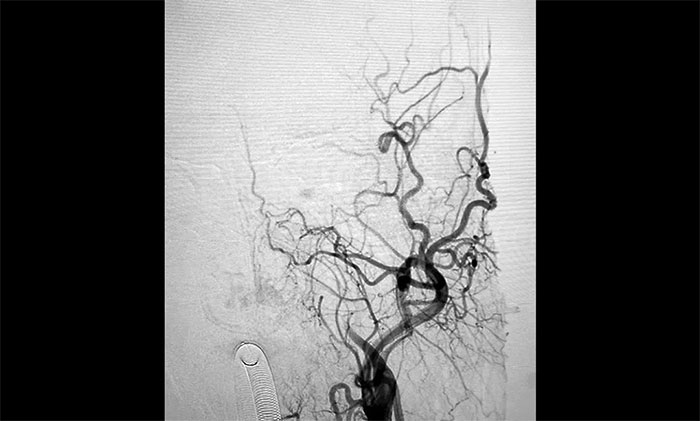

▲術(shù)前DSA影像:左側(cè)頸內(nèi)動(dòng)脈眼動(dòng)脈段以遠(yuǎn)閉塞

術(shù)中腦血管造影可見:左側(cè)頸內(nèi)動(dòng)脈眼動(dòng)脈段以遠(yuǎn)閉塞……余血管未見明顯異常。張琪博士在劉春、周林華、李喆醫(yī)生協(xié)助下,通過右側(cè)股動(dòng)脈穿刺,將微導(dǎo)管、微導(dǎo)絲送達(dá)左側(cè)大腦中動(dòng)脈M1段,經(jīng)多次抽吸+支架拉栓,順利取出血栓。造影顯示,頸內(nèi)動(dòng)脈眼動(dòng)脈段血流恢復(fù)。